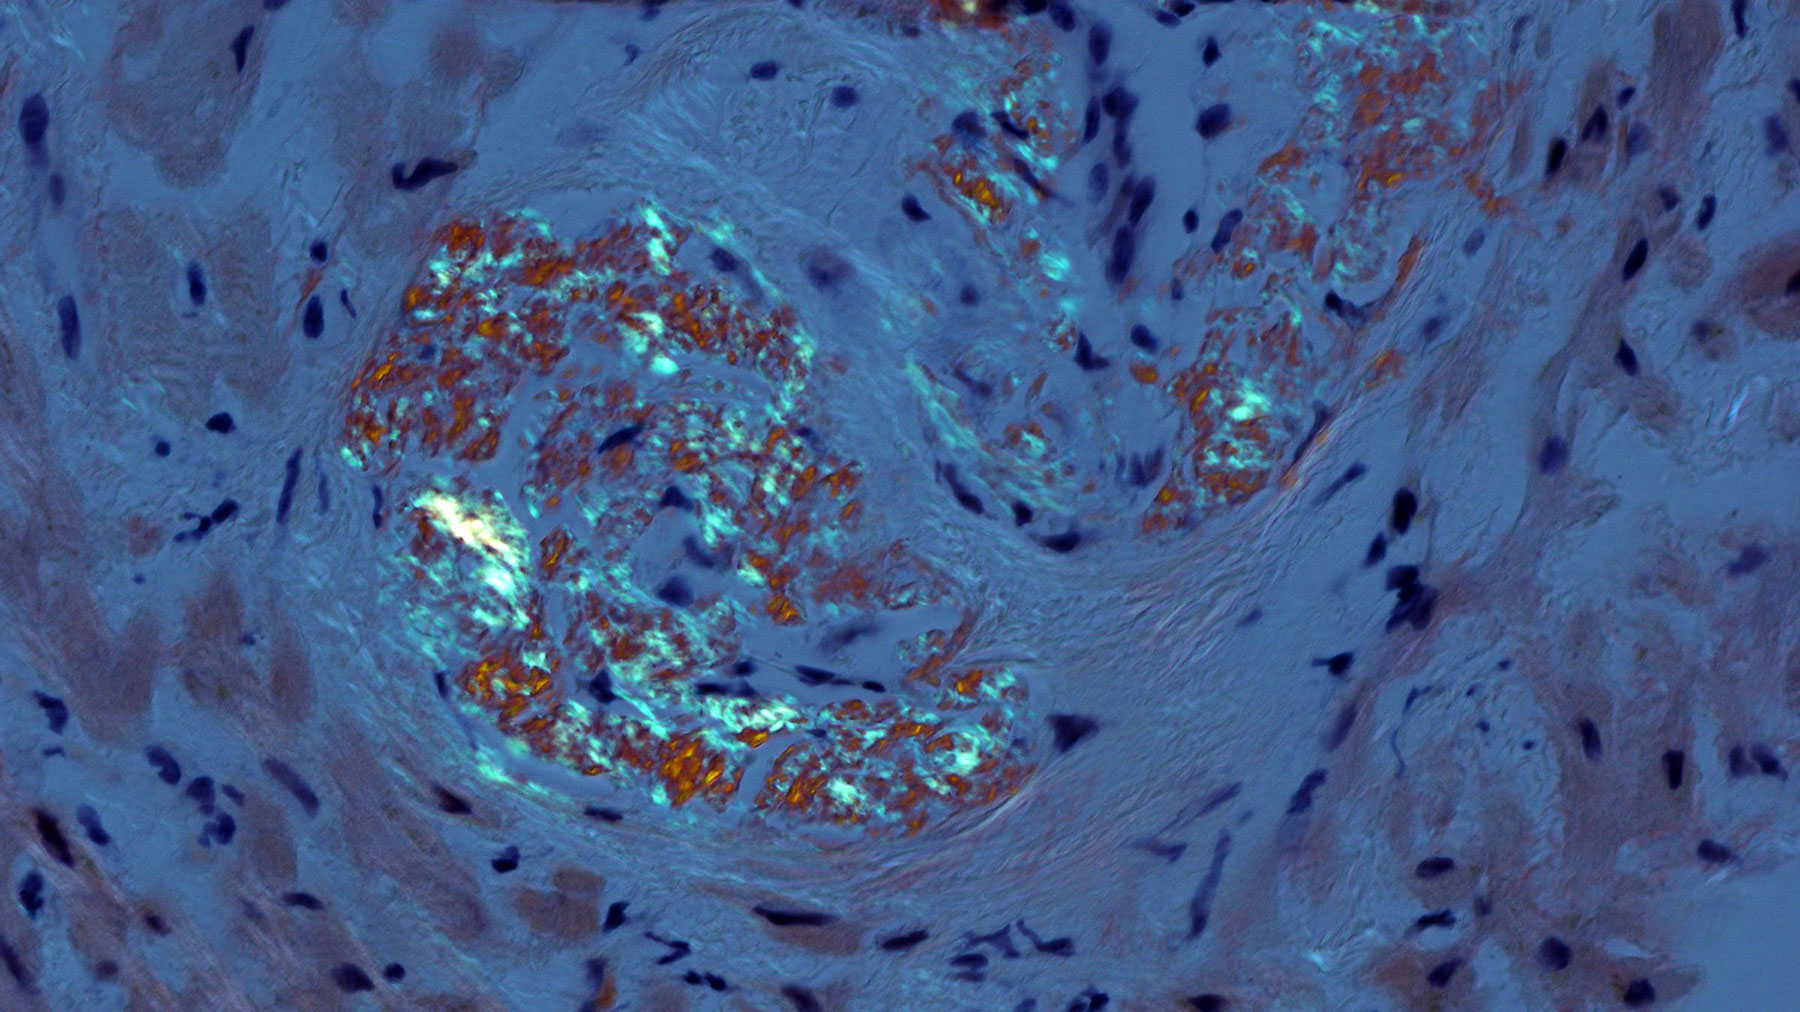

Figure E. Congo Red stain x40

Histology: A heart biopsy was performed and H&E sections (Figures A & B) show myocardial tissue with unremarkable cardiomyocytes and mild to moderate interstitial fibrosis, confirmed by trichrome staining (Figures C and D). The small vessels show moderate wall thickening with accumulation of smudgy, light eosinophilic material with cracking appearance, which stains light purple with the trichrome staining. Congo red staining (Figure E) viewed under polarized light shows apple-green birefringence consistent with amyloid deposits. Electron microscopic examination (Figures F and G) reveal cardiomyocytes and vascular structures surrounded by a fibrillary material (Figure G) consistent in size and appearance with amyloid (n 5-15 nanometer).